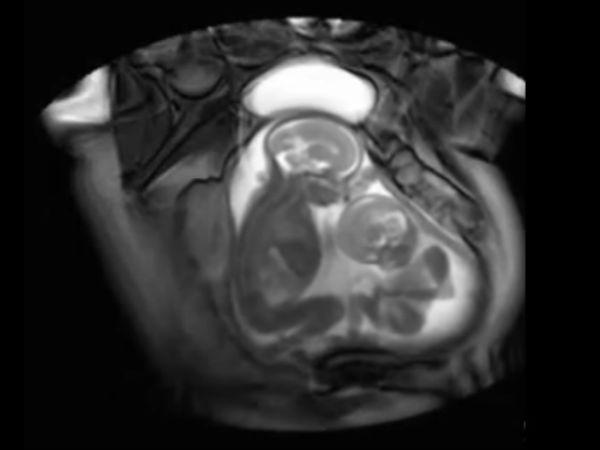

ഇരട്ടക്കുട്ടികള് വയറ്റിനകത്ത് തന്നെ അടിപിടി

ഇരട്ടക്കുട്ടികള് ഗര്ഭപാത്രത്തിനകത്ത് വെച്ച് അടിയും ചവിട്ടും എന്നു വേണ്ട എല്ലാ കലാപരിപാടികളും ഉണ്ട്

വളരെ അപൂര്വ്വമായി മാത്രമേ ഇത്തരം കാഴ്ചകള് ക്യാമറയ്ക്കുള്ളില് പതിയാറുള്ളൂ എന്നാണ് ഡോക്ടര്മാര് പറയുന്നത്. ലണ്ടനില് നടന്ന ഒരു പഠനത്തിനിടെയാണ് ഇടി കൂടുന്ന ഇരട്ടക്കുട്ടികളെ കണ്ടെത്തിയത്.

എം ആര് ഐ സ്കാന്

സിനി എം ആര് ഐ സ്കാന് എന്ന നൂതന വിദ്യയുടെ സഹായത്തോടു കൂടിയാണ് ഇത്തരമൊരു രംഗം ചിത്രീകരിയ്ക്കപ്പെട്ടത്. ട്വിന് ടു ട്വിന് ട്രാന്സ്ഫ്യൂഷന് സിന്ഡ്രോം എന്ന അവസ്ഥയാണ് ഇത്.

പരസ്പരം അടി

രണ്ട് പേരും കൂടി പ്ലാസന്റ ഷെയര് ചെയ്യുമ്പോള് അസാധാരണമായ രക്തകോശങ്ങള് ഉണ്ടാവുന്നു. ഇത് കുട്ടികളില് ഒരാള്ക്ക് പോഷകങ്ങള് കുറവ് കിട്ടാന് കാരണമാകുന്നു.

എന്തിന് വേണ്ടിയാണ് ഇത്തരത്തില് അടി കൂടുന്നതെന്നതാണ് അറിയാത്തത്. ഇനി കിടക്കാന് സ്ഥലമില്ലാത്തത് കൊണ്ടാവുമോ? എന്നാല് അടി കിട്ടുന്ന ആള് അതൊന്നും തിരിച്ച് കൊടുക്കാതെ എല്ലാം കൊള്ളുകയാണ്. എപ്പോഴെങ്കിലും തിരിച്ച് കൊടുക്കാമെന്ന പ്രതീക്ഷയായിരിക്കും.